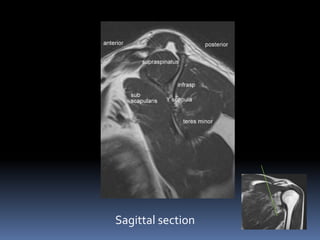

Sagittal section